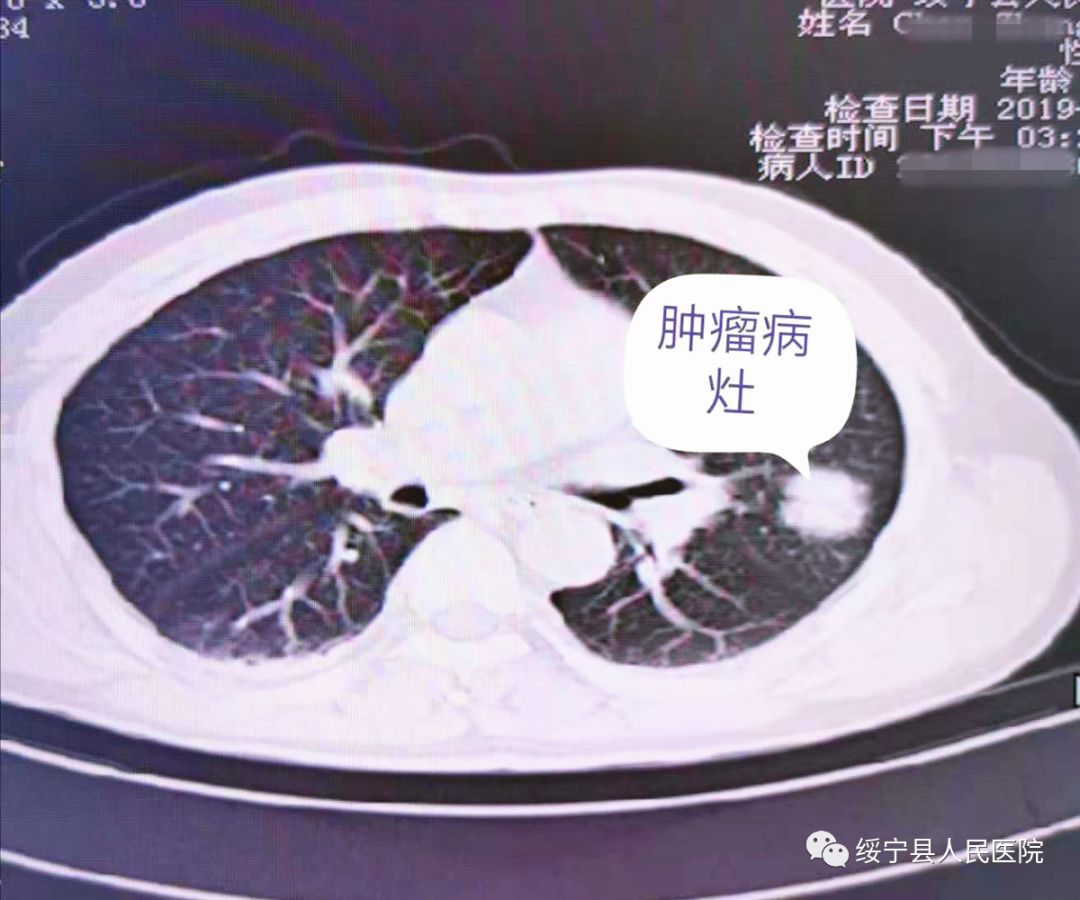

患者陈某某,男性,56岁,因“头胸部外伤后疼痛3小时”入住绥宁县人民医院神经外科,完善胸部CT提示:左上肺占位,倾向于周围型肺癌。

图为胸部CT检查

总结:肿瘤并不可怕,贵在早期发现、早期诊断、早期治疗。该患者有长期吸烟史,本次就诊因外伤入院,行胸部CT检查发现肺部肿瘤,为I期肺癌,发现早、治疗早,大大改善预后及生存质量。